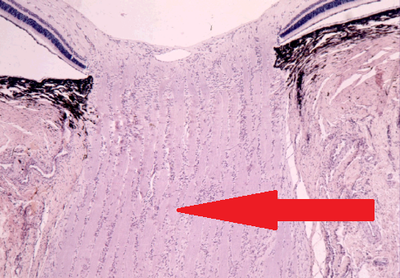

Question 2

Question

Marque la opción correcta de acuerdo a la estructura señalada

Image:

4746bf96-bb4d-4b03-a9da-d5ed26f3094d (image/png)

Answer

Iris

Cuerpo ciliar

Limbo esclero corneal